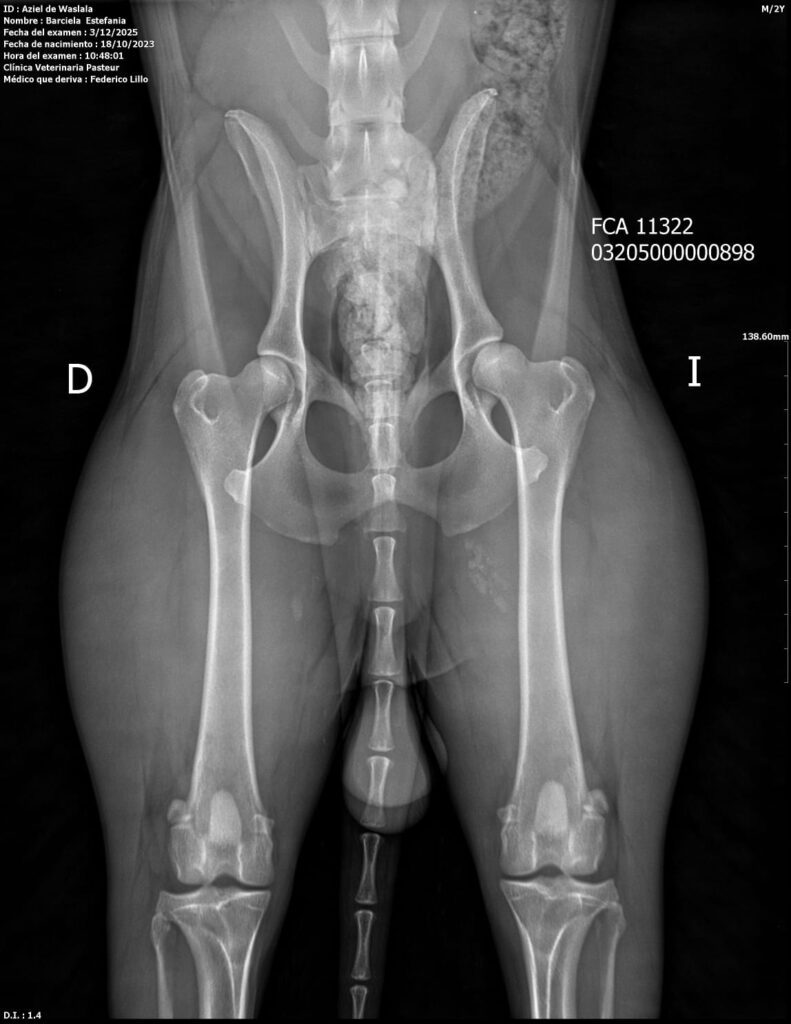

Placas de caderas y codos en La Rienda Border Collie

Realizamos radiografías oficiales de caderas y codos a nuestros reproductores, evaluadas por profesionales veterinarios especializados.

Estos estudios permiten detectar posibles patologías hereditarias, como la displasia de cadera y de codo, ayudando a reducir su incidencia generación tras generación.

✔ Clasificación A en caderas y codos, indicativo de articulaciones sanas y excelente conformación

✔ Clasificación A en codos y B en caderas, siempre informada con total transparencia y criterio de selección responsable